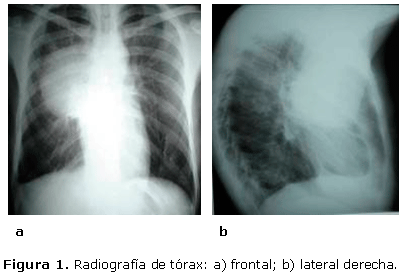

La radiografía de tórax frontal y lateral derecha mostraba una radiopacidad homogénea mediastino pulmonar derecho, de bordes bien delimitados que se situaba en el mediastino anterosuperior y derrame pleural derecho de pequeña cuantía. (Figura 1).

Ante este cuadro clínico y radiológico se ingresó al paciente para comenzar estudio y tratamiento, planteándose como posibles diagnósticos un Timoma y un Síndrome Mediastinal.